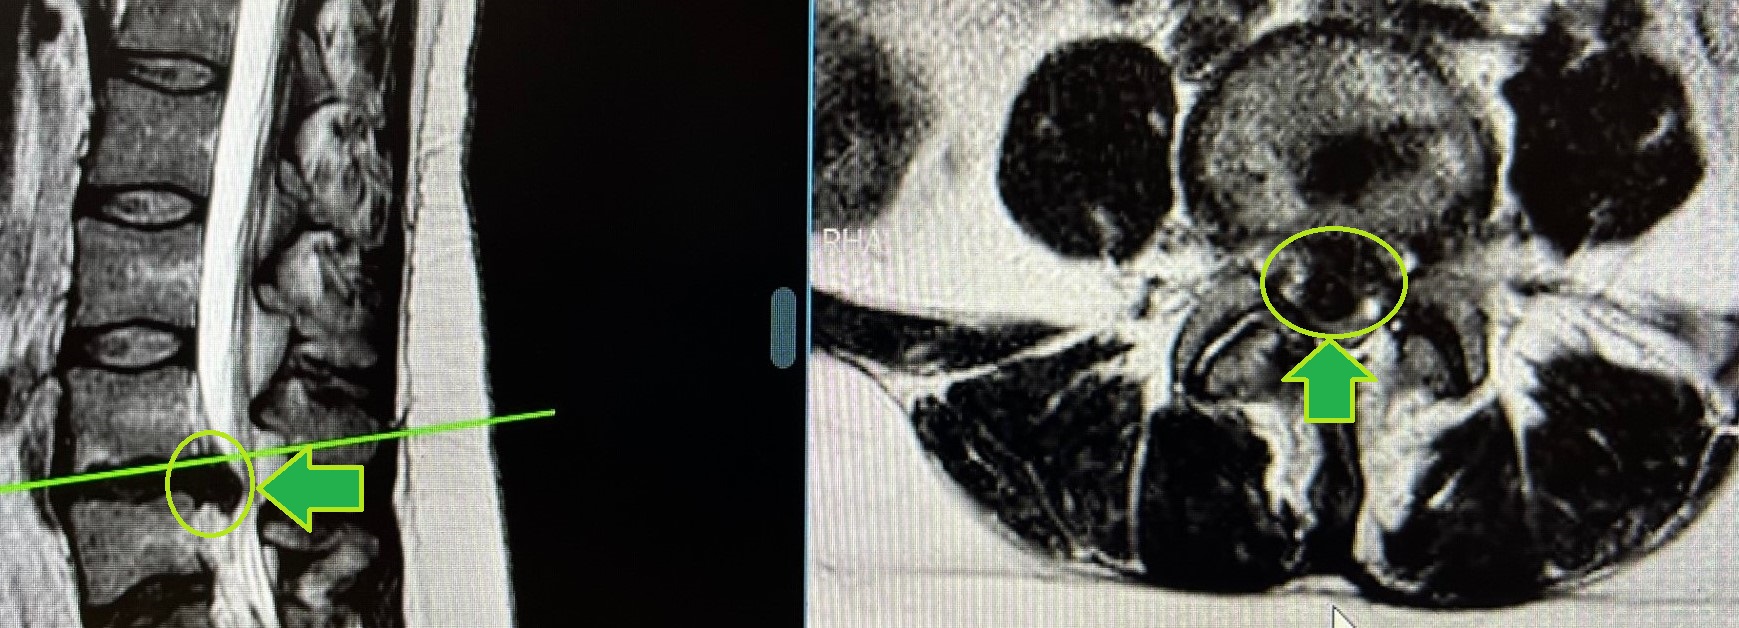

– Ressonância magnética (RM): O exame de imagem mais comum e preciso para uma suspeita de hérnia de disco é a ressonância magnética.

– Microdiscectomia: consiste em retirar o fragmento de disco herniado com auxílio de algum aparelho óptico, como lupas cirúrgicas ou microscópios.

– Discectomia endoscópica: consiste em retirar o fragmento de disco herniado com auxílio de um endoscópio, também pode ser usado para aumentar o espaço do canal vertebral e do forâmen acometido.